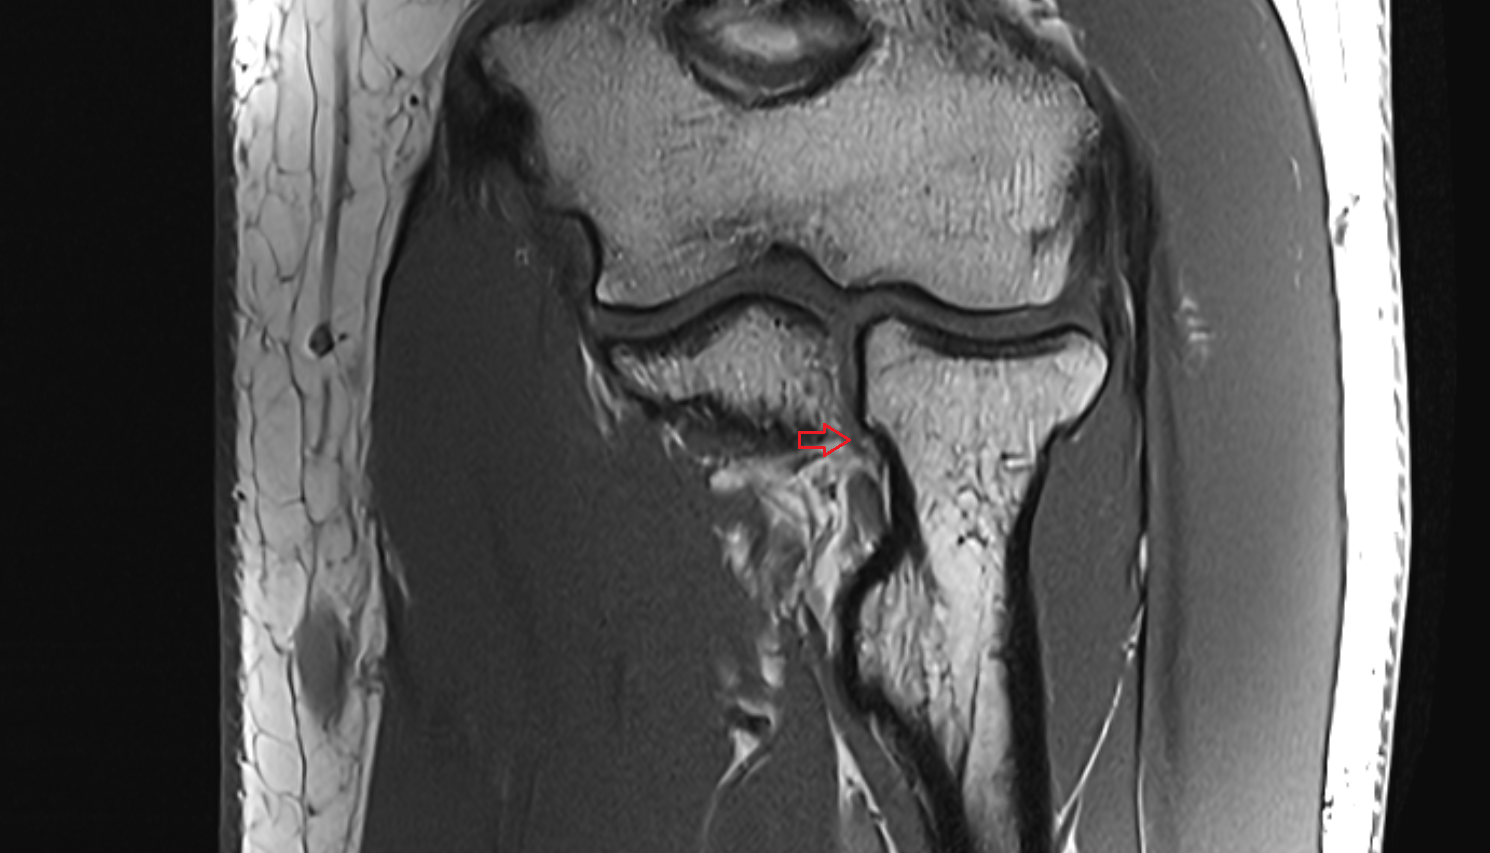

- Medial meniscus

- Lateral meniscus

- Posterior horn of medial meniscus

- Posterior horn of lateral meniscus